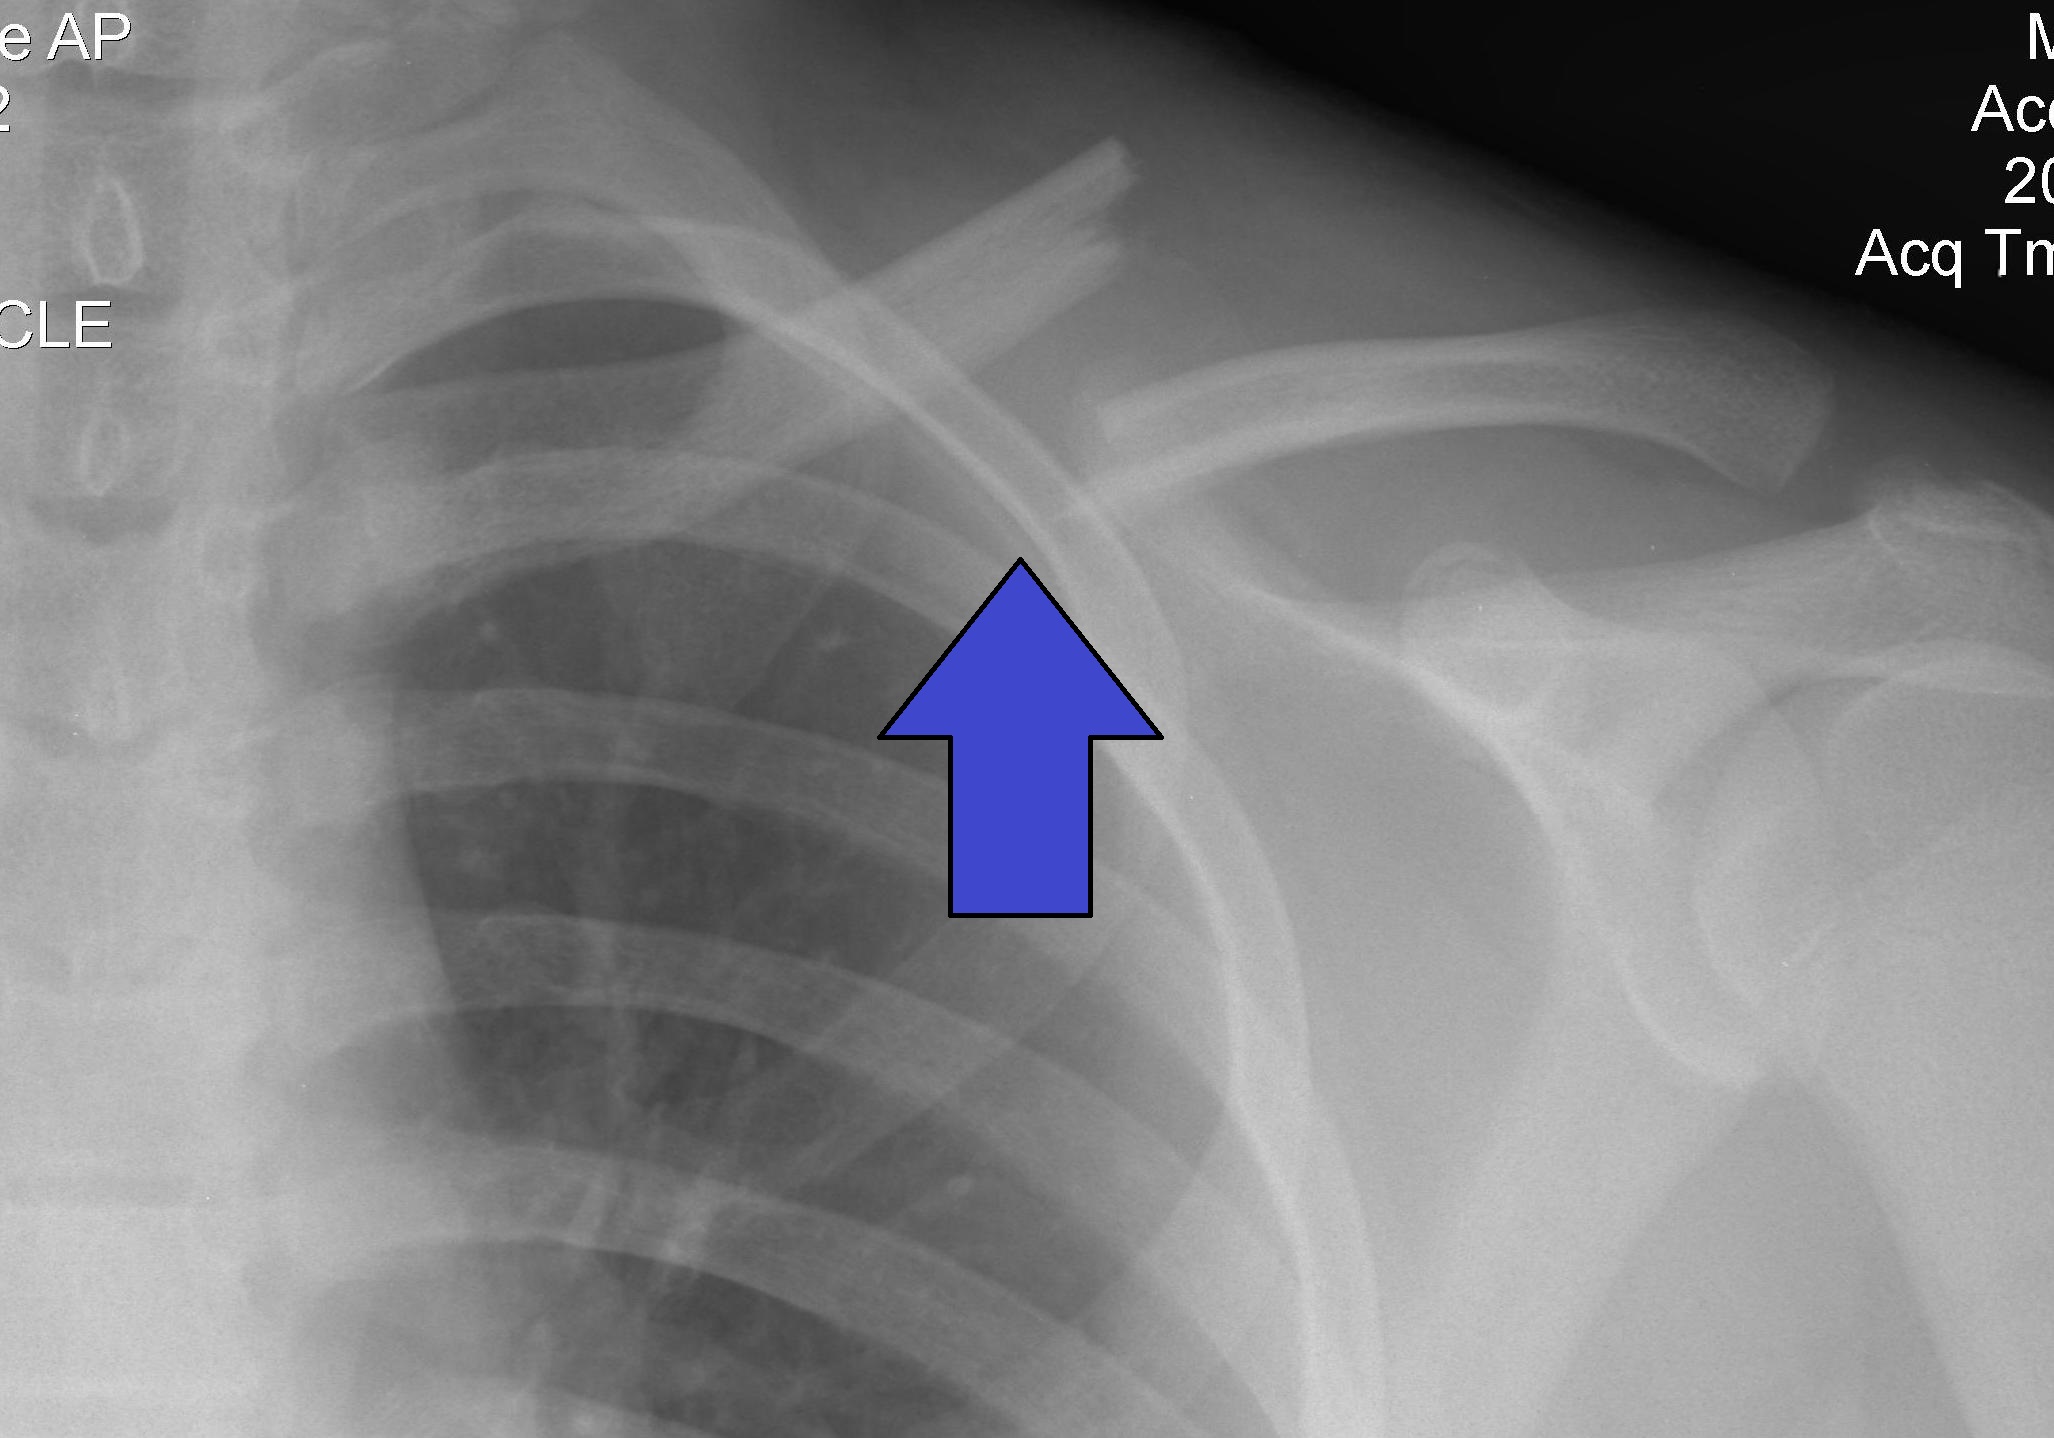

X-Ray image showing a fractured clavicle (collar bone). Clavicle fractures are a one of the most common injuries resulting from falls. This particular fracture occurred during a car accident. of Image Credit: Clavicle Fracture Left uploaded by Majorkev via Wikimedia Commons

[2]